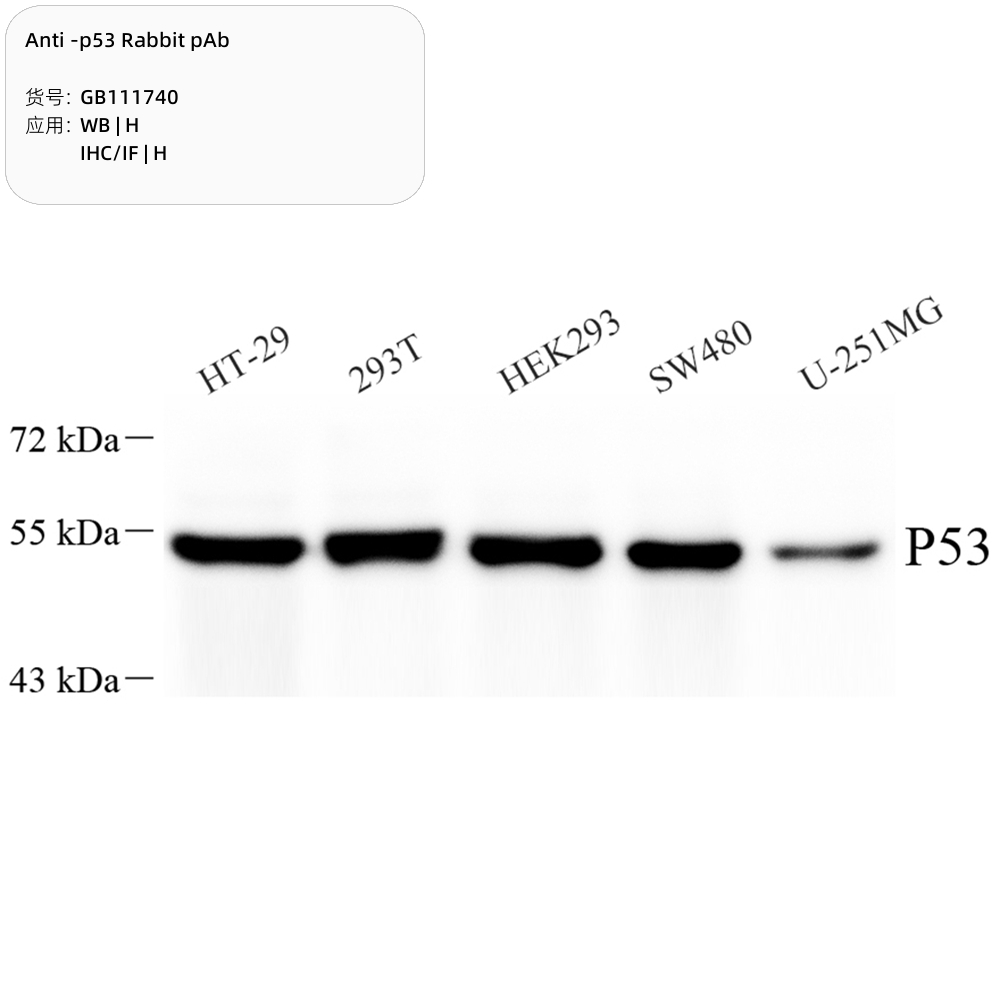

工业油品/胶粘/化学/实验室用品

1050

低价

工业油品/胶粘/化学/实验室用品

1050

低价

Servicebio抗-p53兔pAb抗体Anti-p53 Rabbit pAb,适用WB/IHC/IF,H

淘宝好物 中科生物

购买 -